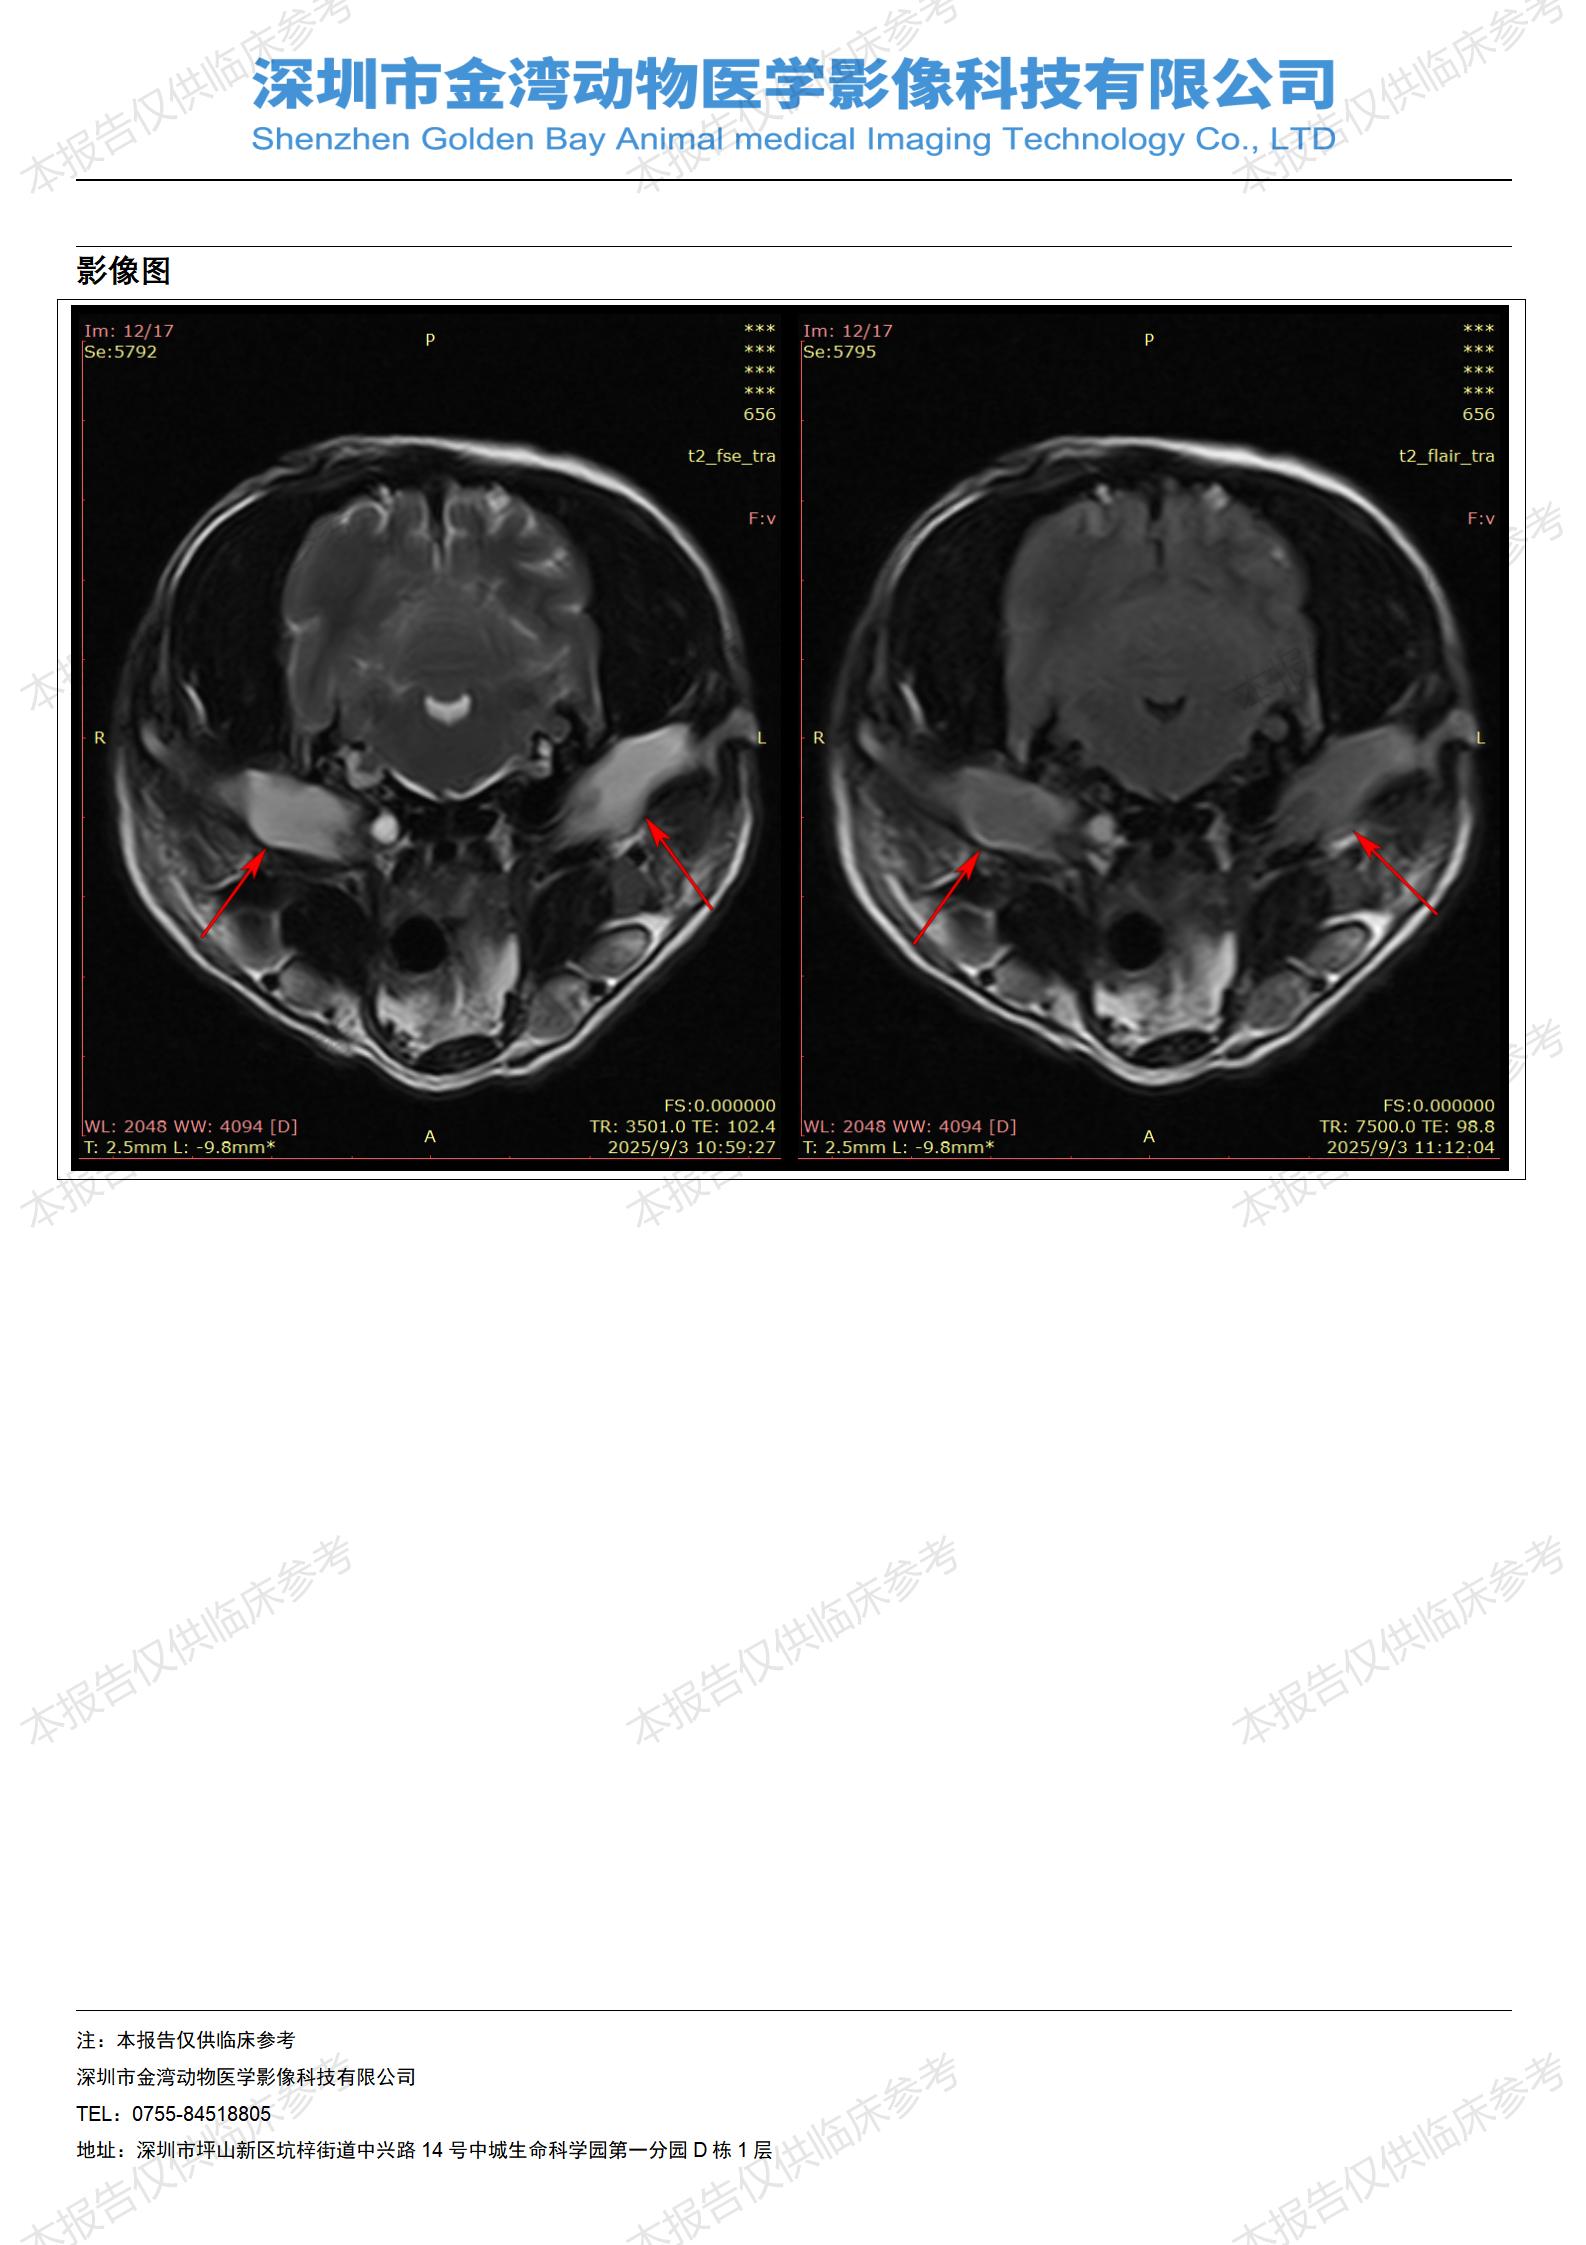

金石医疗MRI影像诊断案例:一例狗双耳流脓的诊断报告